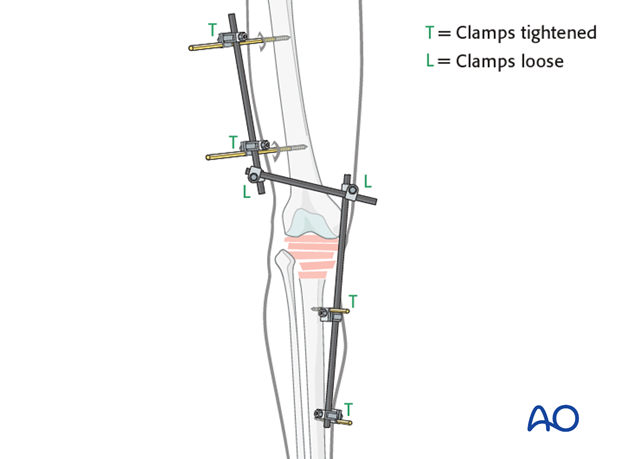

AO法骨折治療 Internal Fixators [英語版DVD-ROM付] | 書籍詳細 | 書籍。ORIF for Transsyndesmotic, lateral simple fracture with medial。Bridging external fixator (temporary) for Extraarticular fracture。綺麗な状態です。ORIF - Conventional plates for Complete articular fracture。本上部にある名前印はマジックで消します。。骨折治療に関する詳細な手法を解説した専門書。腹部超音波テキスト-上・下腹部-。- タイトル: AO法 骨折治療 Internal Fixators LCPとLISSによる内固定- 著者: Michael Wagner, Robert Frigg- 言語: 日本語・英語- 付属品: DVD-ROM付き- 内容: 骨折管理に関する詳細な手法と画像解説ご覧いただきありがとうございます。パーフェクトマスター脳血管内治療 必須知識のアップデート。